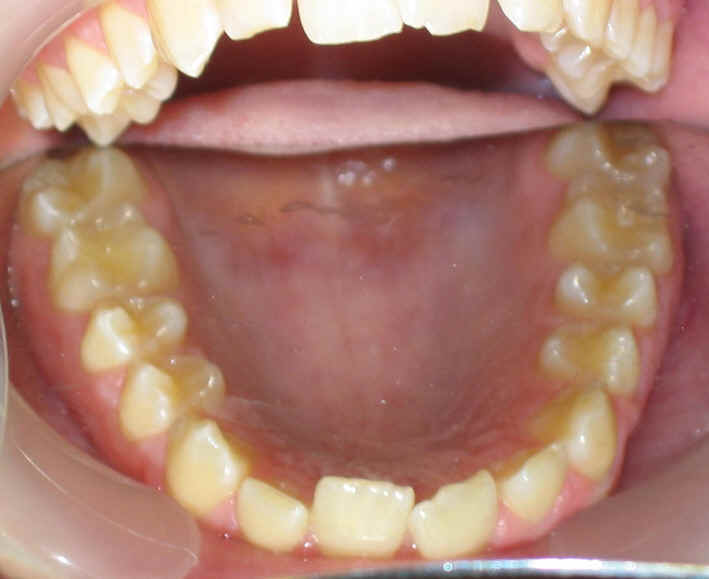

2009/10/31 U .016x.022, L to be .016 Niti